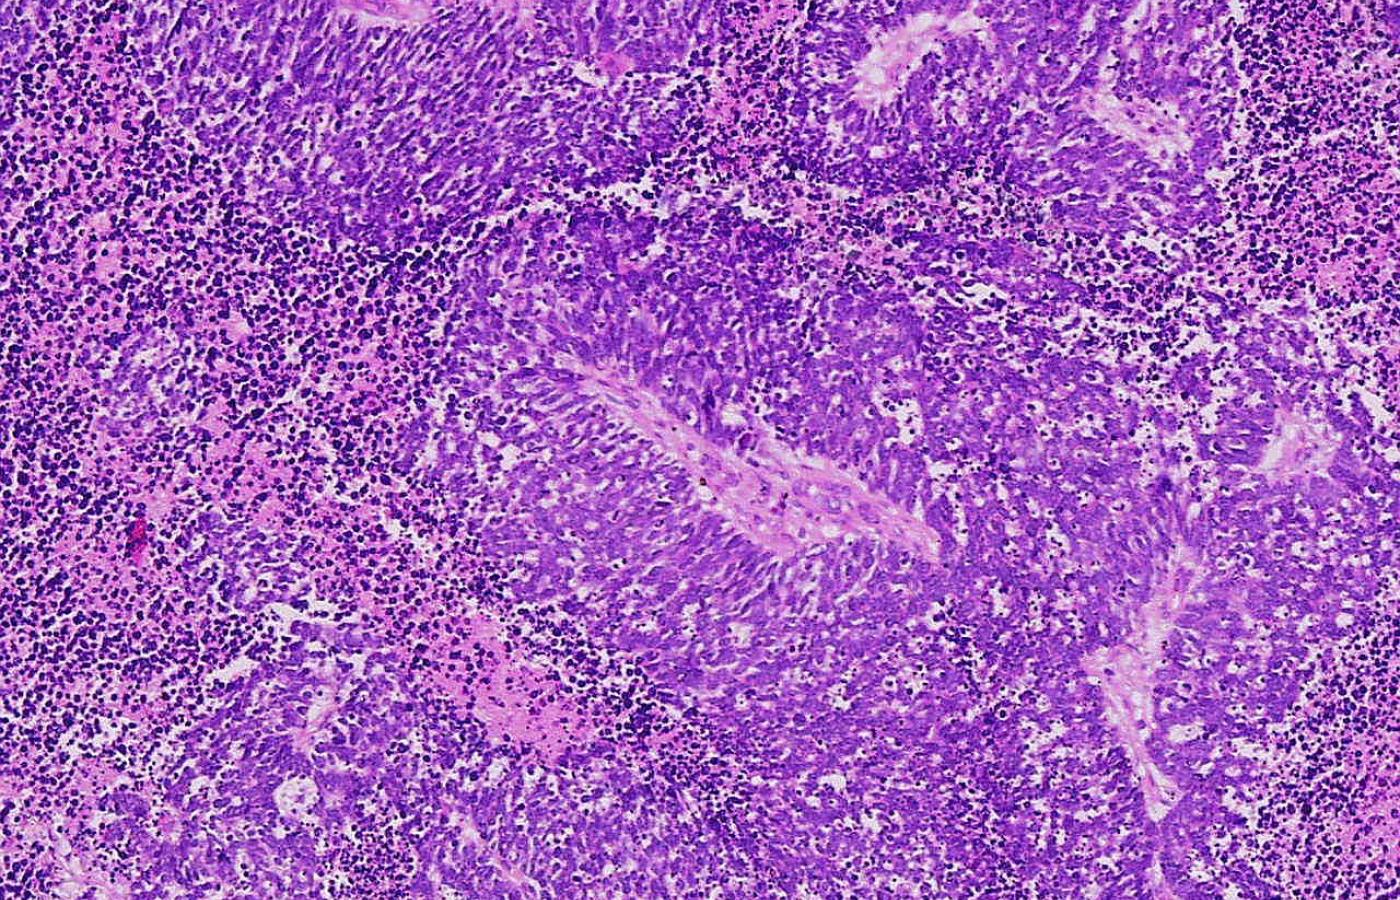

Limfocyty (zaznaczone na biało) przywierają do komórki raka, rozpoznając obecne na jej powierzchni białka. Limfocyty (zaznaczone na biało) przywierają do komórki raka, rozpoznając obecne na jej powierzchni białka. SPL / East News

Drobnokomórkowy (anaplastyczny) rak płucWikipedia Drobnokomórkowy (anaplastyczny) rak płuc

Idea tego leczenia sprowadza się do odblokowania uśpionych limfocytów, aby z większym impetem atakowały raka. Nasz naturalny nadzór immunologiczny codziennie wyszukuje w organizmie komórki, które mogą zezłośliwieć. Dlatego u chorych po przeszczepach, u których trzeba usypiać układ odporności, aby nowy narząd mógł się zaadaptować, ryzyko choroby nowotworowej wzrasta aż 7-krotnie. Limfocyty, główni żołnierze tej naturalnej obrony, za pomocą wyspecjalizowanych receptorów, rozpoznają na powierzchni komórek nowotworowych specyficzne antygeny, a następnie indukują kaskadę przemian prowadzących do zniszczenia komórek guza.